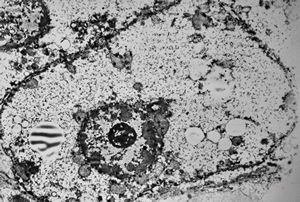

M,3y. | normal hepatocyte